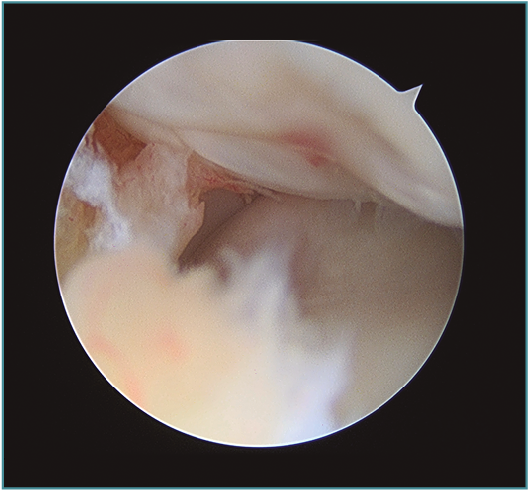

Los portales más adecuados son el anteromedial proximal para la óptica y el anterolateral, el anterolateral proximal y el mediolateral directo o soft-spot (Figura 4) como portales de trabajo. Los portales anteromediales permiten una excelente visualización de la cámara anterior, de la superficie articular de la cabeza radial, del cóndilo humeral, de la apófisis coronoides y de la cápsula anterior y lateral (Figura 5). A este nivel suelen observarse la gran mayoría de los cuerpos libres articulares que en ocasiones se encuentran en la zona lateral y posterior del codo (Figura 6).

Figura 6. Abundante sinovitis y cuerpo libre alojado en cámara anterior en un paciente con lesión osteocondral de tipo IV de la International Cartilage Repair Society (ICRS).